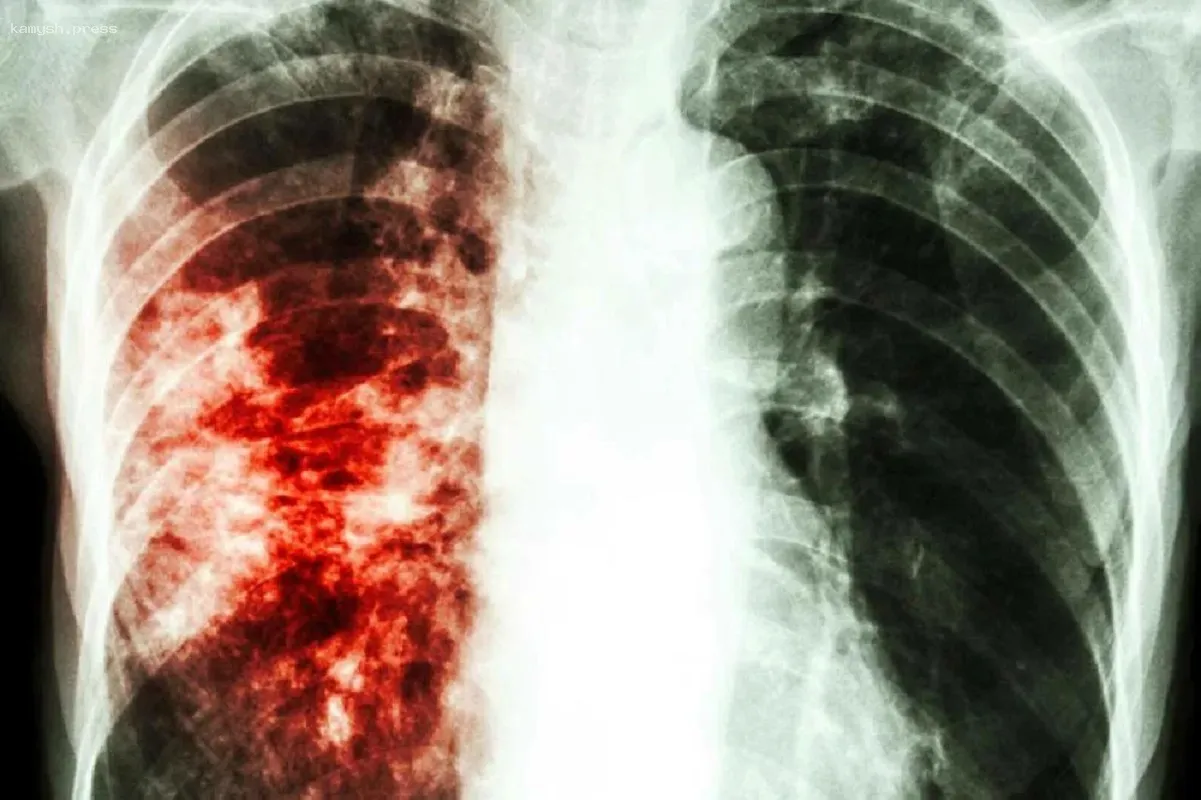

CCB: открыта группа молекул, уничтожающая туберкулезные бактерии новым способом

Известно, что данный тип бактерий туберкулеза в процессе эволюции развил жесткую устойчивость к антибиотикам. По данным научного журнала Cell Chemical Biology (CCB), этот факт многократно усложняет терапию опасного заболевания. На сегодня в арсенале врачей всего лишь несколько препаратов более-менее эффективных в отношении резистентных штаммов.